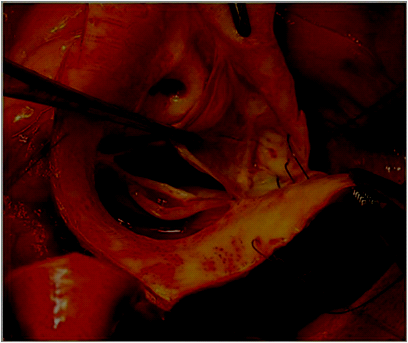

Covering of the aortic root with three patches in bovine pericardium: Three pericardial patches (one for each sinus) are fixed to the annulus by three subannular stitches, placed under each commissure. The patches are fixed to one another with the same subannular stitch. The distal end of these patches are fixed at the level of sinotubular junction between one another and with commissural aortic wall (Figure 6) (Figure 4 & 7) creating a periaortic wall of the aortic root. The patches are incised over the left and right coronary arteries not to cause compression. Direct end-to-end anastomosis between neo aortic root and ascending aorta is then performed.

Figure 6 Covering of the aortic root wall with three patches in bovine pericardium.

Figure 7 Covering of the aortic root with three patches in bovine pericardium.